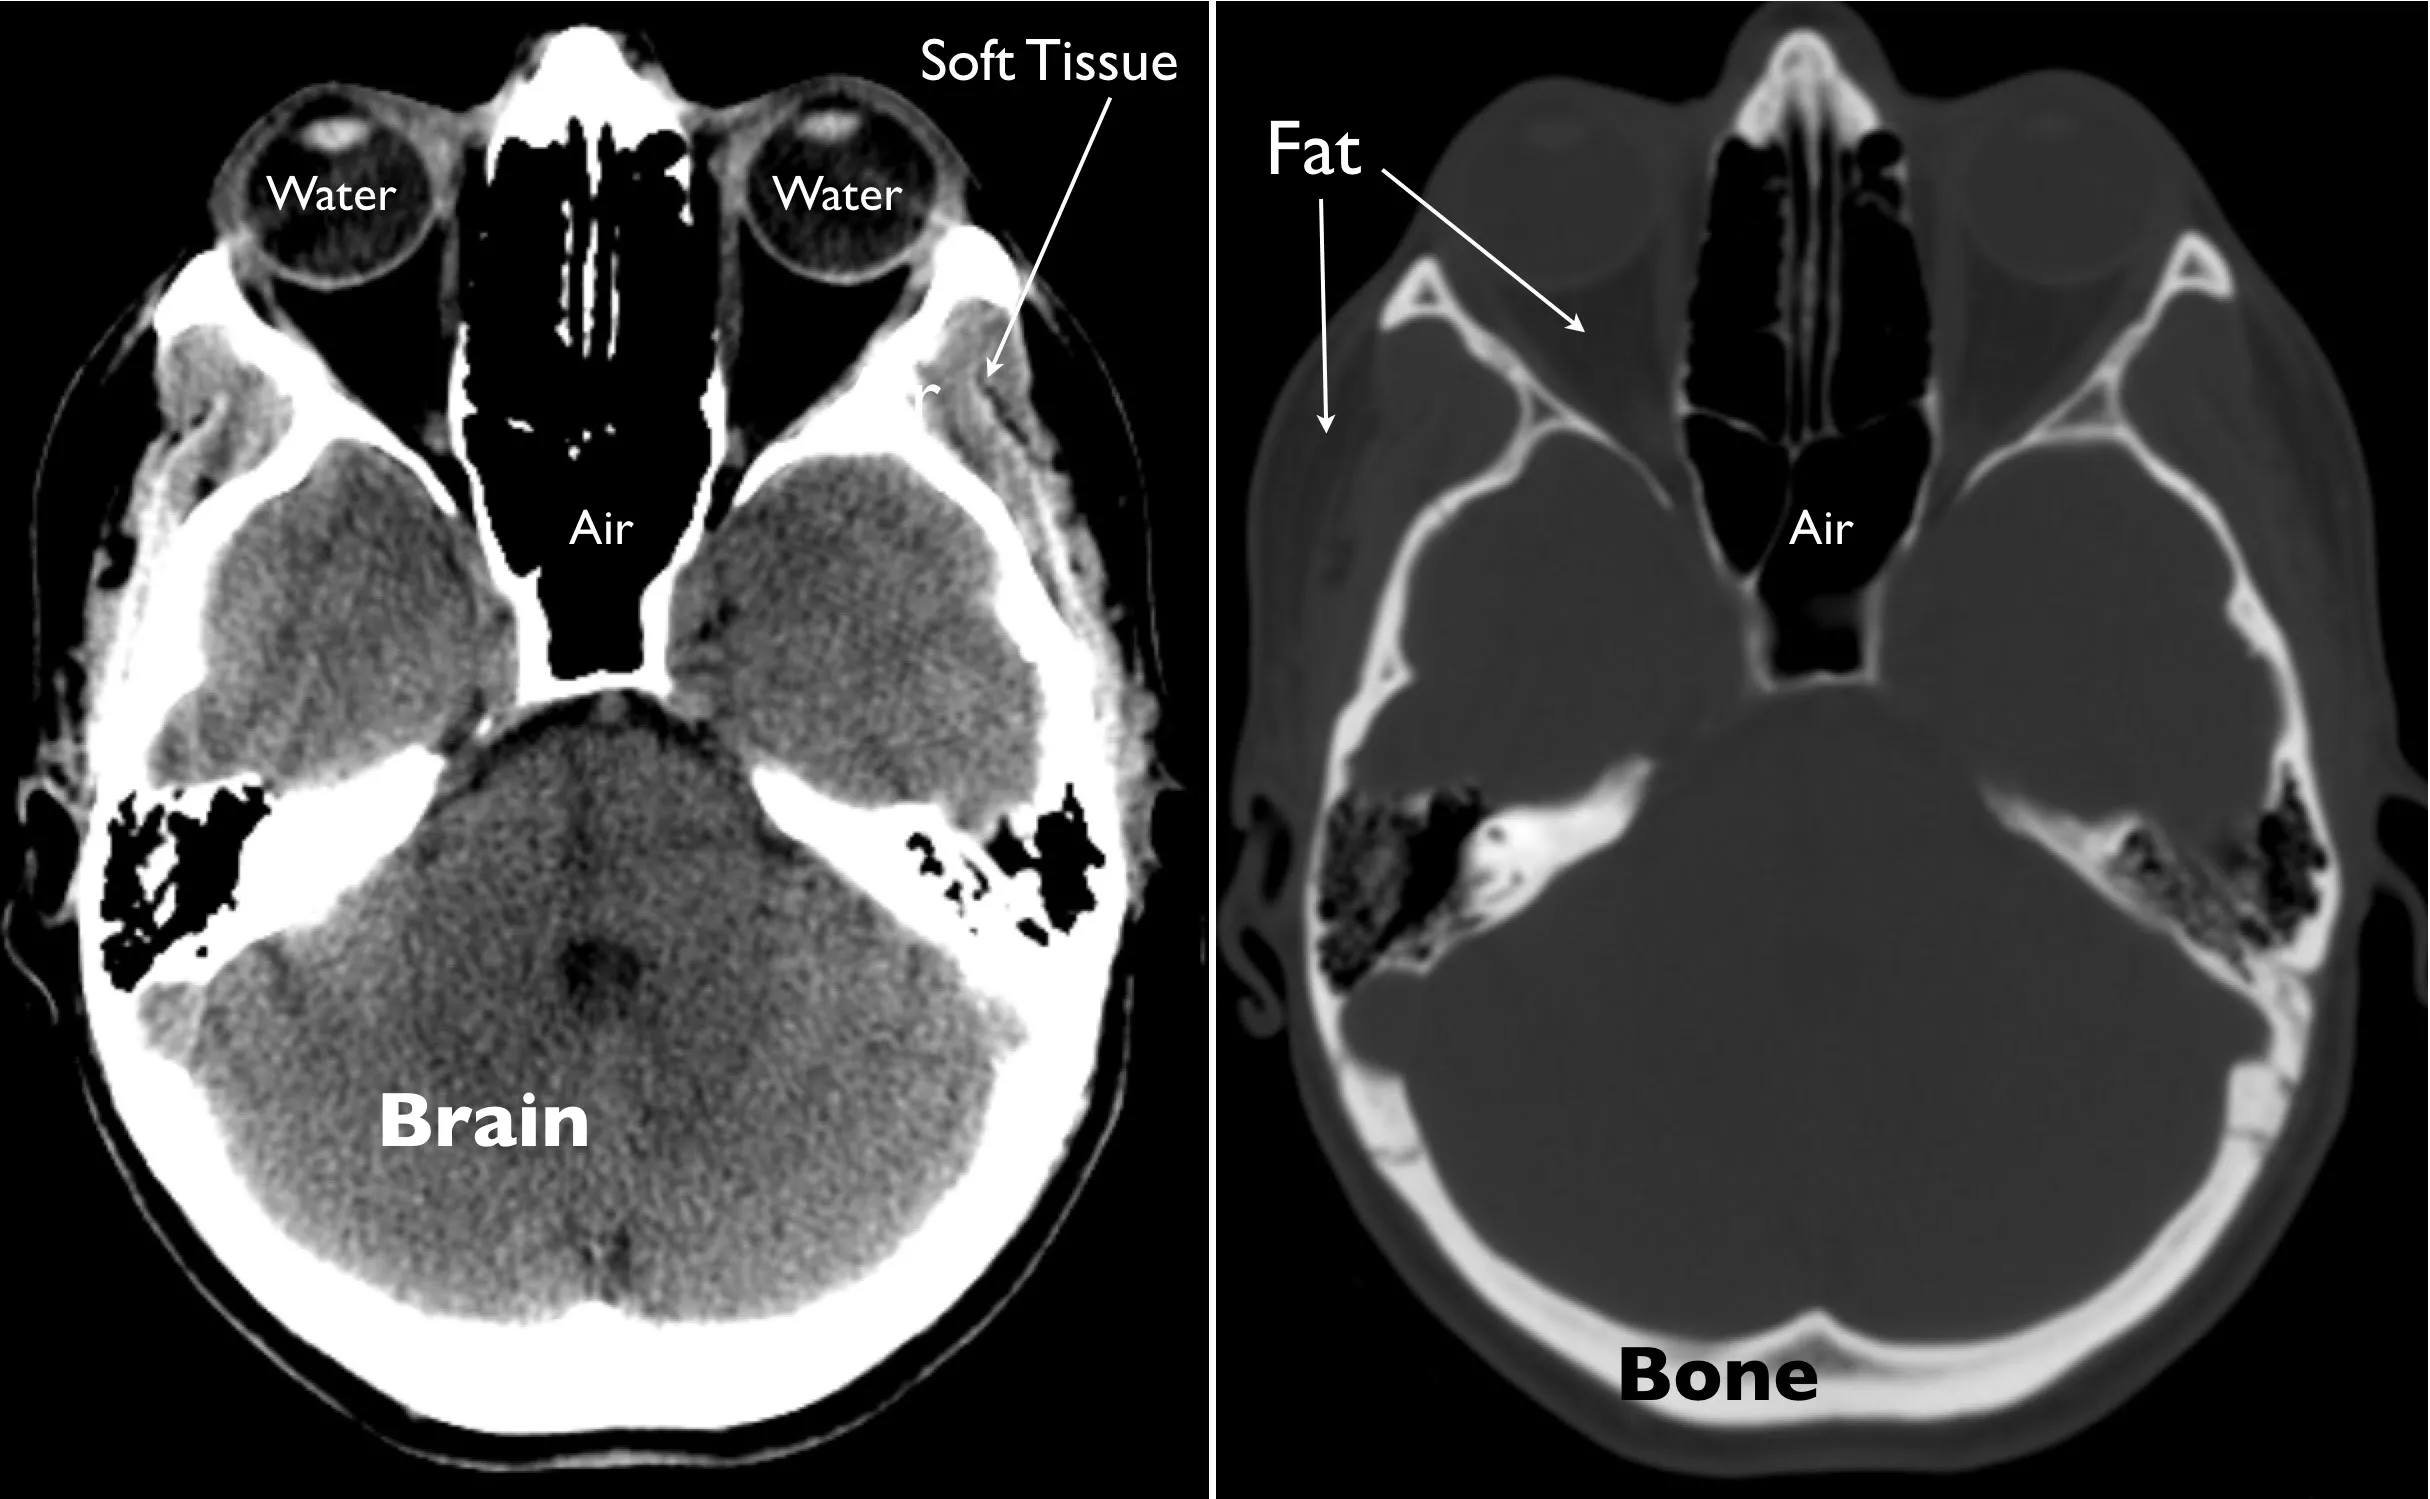

side-by-side axial CT images of the head showing a brain window on the left and a bone window on the right, with labeled areas for soft tissue, water, fat, and air

A single slice from a normal head CT at brain window (left) and bone window (right) settings. Arrows indicate tissues of different density, including water, fat, soft tissue and bone.

The primary physical quantity that is captured with CT is density, or mass per unit volume. Prior to display and storage of CT images, pixel intensities are mapped to a standard numerical scale to allow reliable discrimination between different densities of tissue such as air, water, fat, bone, and various brain constituents. When the images are reviewed on a computer, the intensities are further modified by a process referred to as windowing in order to optimally depict the density of different tissues for visual display. Extremely dense material, such as metal or bone, appears bright on CT images, whereas tissue that is less dense, like fat or water, appears dark.